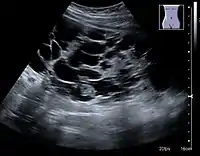

Complex cysts can have membranes dividing the fluid-filled center with internal echoes, calcifications or irregular thickened walls. The complex cyst can be further evaluated with Doppler US, and for Bosniak classification and follow-up of complex cysts, either contrast-enhanced ultrasound (CEUS) or contrast CT is used (Figure 6). The Bosniak classification is divided into four groups going from I, corresponding to a simple cyst, to IV, corresponding to a cyst with solid parts and an 85–100% risk of malignancy.[1] In polycystic kidney disease, multiple cysts of varying size in close contact with each other are seen filling virtually the entire renal region. In advanced stages of this disease, the kidneys are enlarged with a lack of corticomedullary differentiation (Figure 7).[1]

Figure 7. Advanced polycystic kidney disease with multiple cysts.[1]